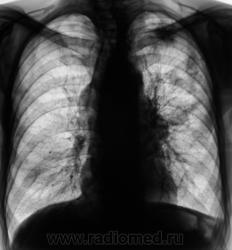

Отдельные снимки этого пациента выставлялись на сайте, но мы никогда не имели полного "набора", так как рентгенологические исследования проводились в трех ЛПУ - у нас и в двух ЛПУ областного уровня (спец. ЛПУ), где пациент получал специфическое лечение. Сегодня, мы имеем полный набор снимков, и мне показалось целесообразным выставить, именно, динамику....

Пациент был взят на контроль в 2009 году, было произведено дообследование в виде томографии в стандартных срезах, был заподозрен очаговый туберкуулёз, который был подтвержден " в области" и пациент был взят на учет. Было назначено специфическое лечение.

Через некоторое время было произведено плановое контрольное обследование.

Следующее плановое исследование.

После проведения данного исследования возникло подозрение, что "это" не туберкулёз, или имеет место сочетанная патология.

После первой госпитализации в областном спец. ЛПУ, при выписке, в виде контроля динамики, была сделана рентгенограмма в прямой проекции, которая, на мой взгляд, имеет определенный интерес.